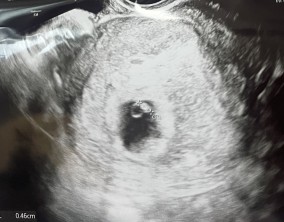

조심스러운 기쁨이 안도가 되기까지

이유정 원장님께서 차분하고 사실적으로 치료 과정과 정보를 설명해 주셔서 불안한 마음이 많이 줄어들었습니다. 미디어에서 접했던 이야기들로 걱정이 컸던 만큼, 현실적인 설명…